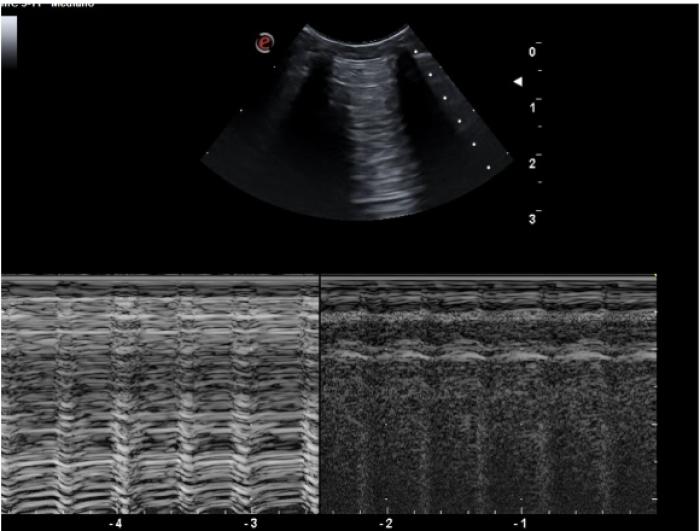

Pulso pulmonar

Es la transmisión del latido cardíaco a través del tejido pulmonar. Aunque es considerado un movimiento normal dentro de la exploración pulmonar con ultrasonido, especialmente en regiones próximas al corazón, lo cierto es que cuando se visualiza con facilidad es posible que exista una mayor consolidación pulmonar sin llegar a la superficie pleural, el aumento de peso del lóbulo transmite mejor dicho movimiento y lo hace más evidente. Su visualización excluye el neumotórax en el área observada.

Puede evaluarse tanto en modo M como en modo B (Figura 7) (Vídeo 3).